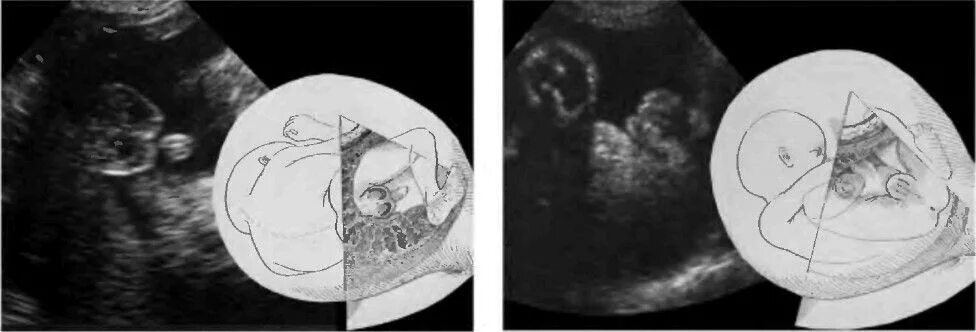

Может ли узи ошибиться в поле